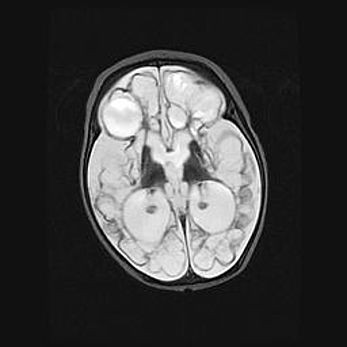

Церебральная ишемия II.

Возраст: 5 дней

Вес: 3400 г

Пол: женский

Окружность головы: 35 см

Срок гестации: 39 недель

Церебральная ишемия – это заболевание, характеризующееся недостаточностью (гипоксией) либо полным прекращением (аноксией) снабжения мозга кислородом по причине закупорки одного или нескольких сосудов. Это приводит к  что метаболическим расстройствам различной степени тяжести в тканях головного мозга, развитию коагуляционных некрозов и гибели нейронов.